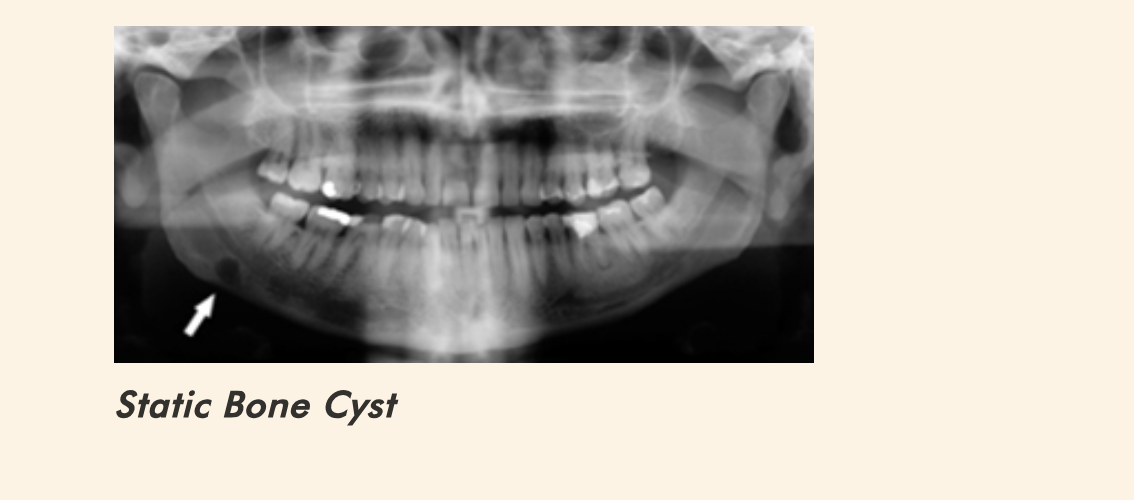

What is a static bone cyst (Stafne defect)?

A pseudocyst presenting as a developmental bone depression, often containing salivary gland tissue.

Why is a Stafne defect not a true cyst?

It lacks an epithelial lining.

Where is a static bone cyst typically located?

Below the mandibular canal near the angle of the mandible.

How does a static bone cyst appear radiographically?

Well-defined radiolucency below the mandibular canal.

What is the treatment for a static bone cyst?

No treatment required; it is asymptomatic and non-expansile.